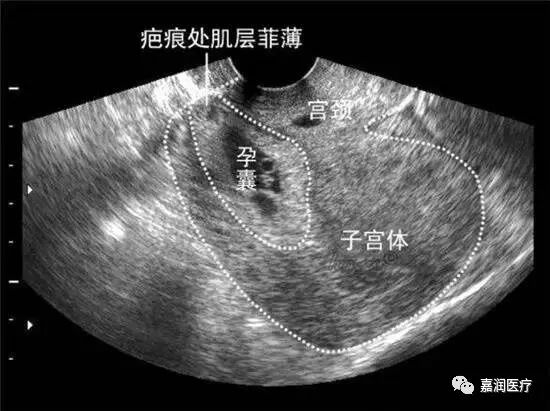

丈夫赶紧陪小西到美国泽尔西西医疗集团哈尔滨嘉润医院妇科门诊就医,经彩超检查示:剖宫产切口瘢痕处有妊娠囊回声!小西是怀孕了没错,但是这“孕囊”却长的不是地方,不能留!

瘢痕妊娠宫外孕的一种特殊类型是指有过剖宫产史的女性在再次妊娠时,孕囊着床在子宫原疤痕处,可导致中晚期子宫破裂及大出血而危及生命,是一种罕见但却异常凶险的急症,简单地说,就是胎儿长到了不该长的地方!

因为子宫瘢痕处的结缔组织较薄、且由于弹性差,很容易被撑破!一旦确诊胚胎着床在子宫疤痕上,就要尽快终止妊娠!